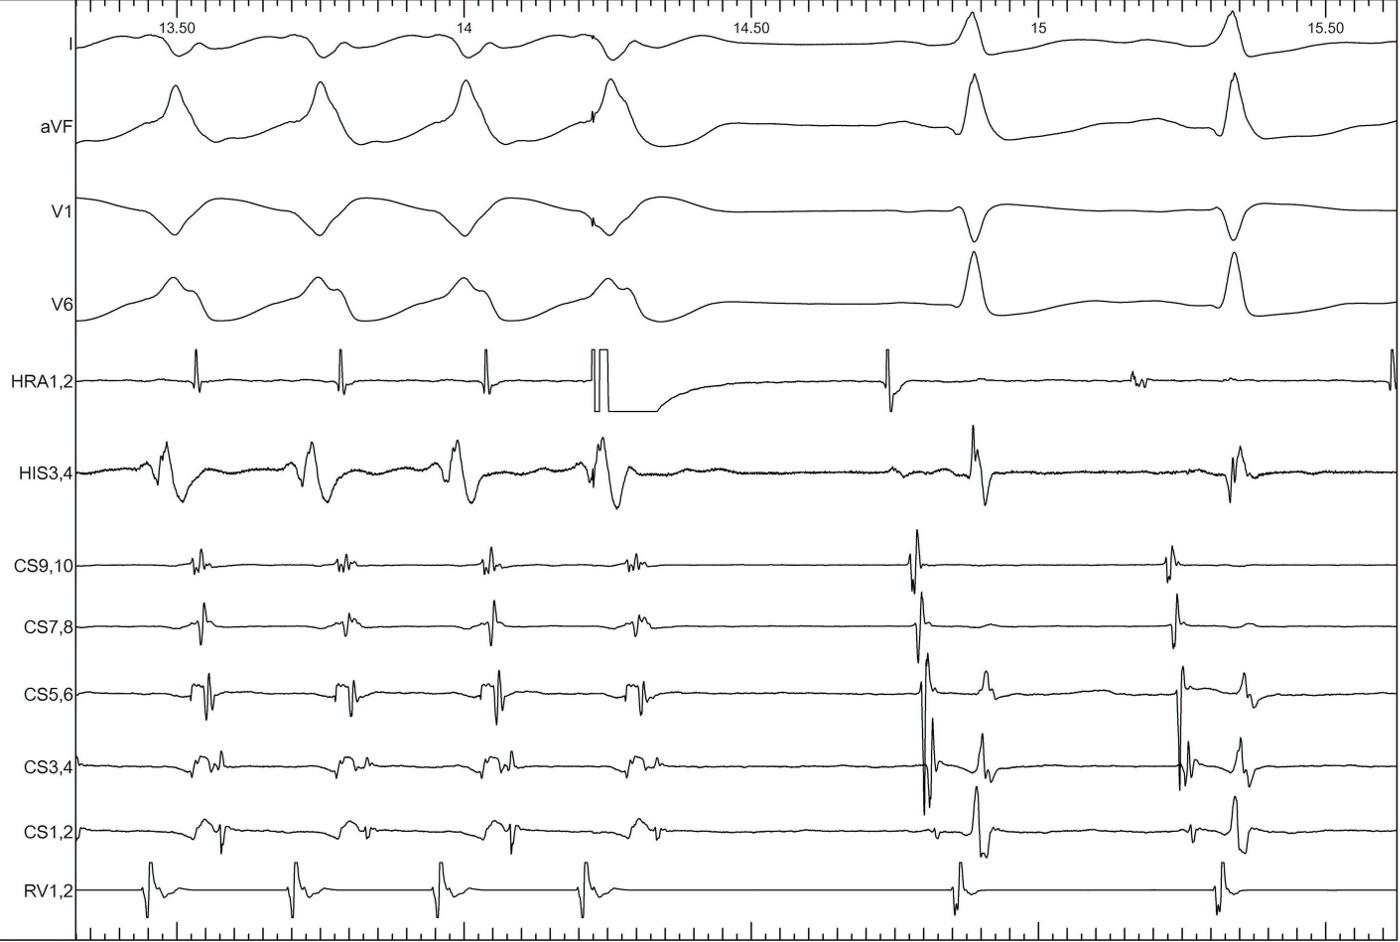

SA-VA

vav_avrt.jpg

VAV - AVNRT or AVRT ?

vav_atypical_vnrt.jpg

sa_va.jpg